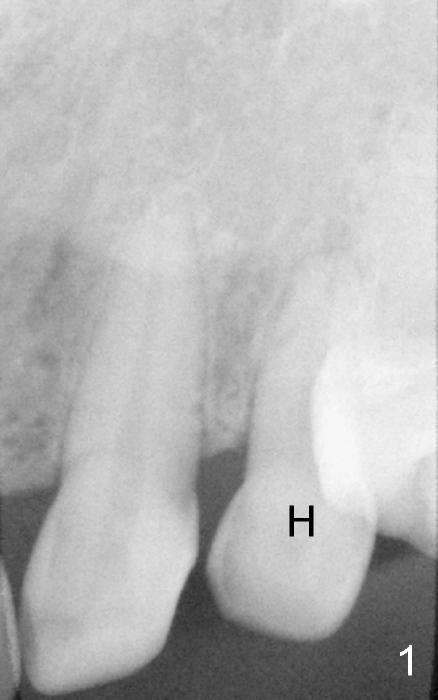

The upper left deciduous canine of a lady in her early forties looks functional 9 and 5 years ago (Fig.1,2). She wanted to close the diastema mesial to the deciduous tooth (Fig.2 *). The tooth was prepared for a provisional (Fig.3 P) and definitive restoration (Fig.4 C). The tooth becomes mobile 4 years post cementation (Fig.5).